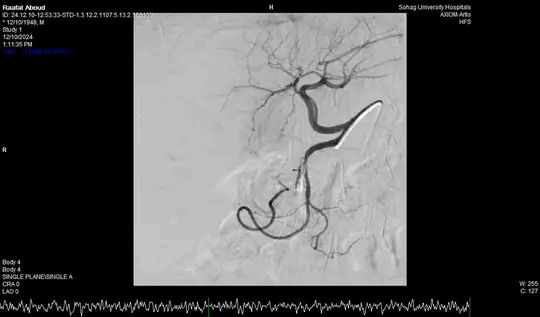

وأضاف الدكتور أحمد كمال المدير التنفيذي للمستشفيات الجامعية انه بعد اجراء الفحوصات للمريض تبين وجود قرحة كبيرة بالاثني عشر وشريان نازف، حيث نجح الفريق في التحكم المبدئي بالنزيف عن طريق تركيب مشبك معدني بالمنظار وحقن للقرحة النازفة، ثم تم استدعاء فريق أطباء وحدة الاشعة التداخلية علي الفور وتم عمل غلق للشريان النازف بشكل عاجل من خلال جهاز القسطرة.

وأوضح الدكتور محمد زاكي رئيس قسم الأشعة أن مثل هذه الحالات تعد من الطوارئ الطبية الخطيرة والتي تستوجب عمل قسطره شريانية عاجلة لغلق الشرايين النازفه مشيراً أن وحدة الأشعة التداخلية تم تزويدها بجهاز أشعه محوري متقدم لاجراء مثل هذه الحالات، وأن هذا النجاح هو نتيجة لتعاون أقسام المستشفي مع وحدة الأشعة التداخليه لتقديم خدمة مميزه للمرضي.